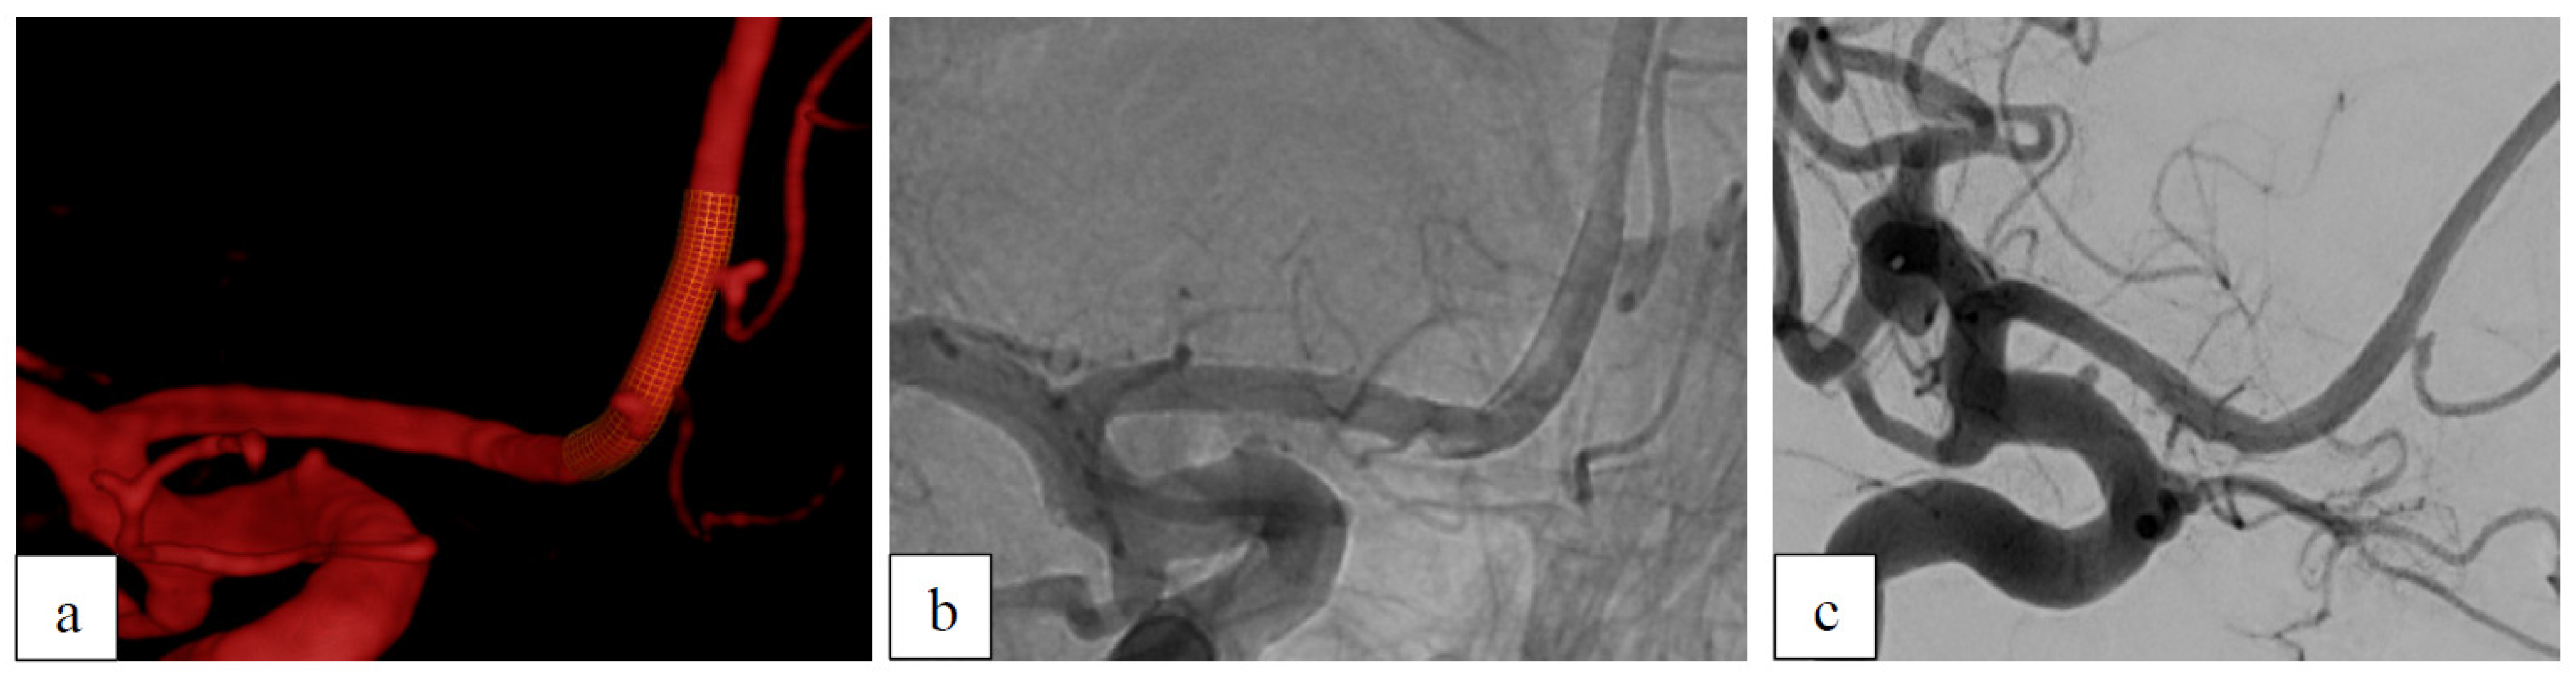

Case 3: Recurrent Aneurysm After Clipping

| 52 | m | AcomA | - | saccular | no | coiling | ASA+ Clopidogrel | - | 12 | D1 |

| 71 | f | AcomA | - | saccular | no | clipping+ coiling | ASA+ Clopidogrel | C2 | 6 | D1 |

| 70 | f | AcomA | - | saccular | no | clipping | ASA+ Clopidogrel | D1 | 7 | D1 * |

| 3 | 70 | f | AcomA | - | saccular | no | clipping | ASA+ Clopidogrel | D1 | 7 | D1 * |